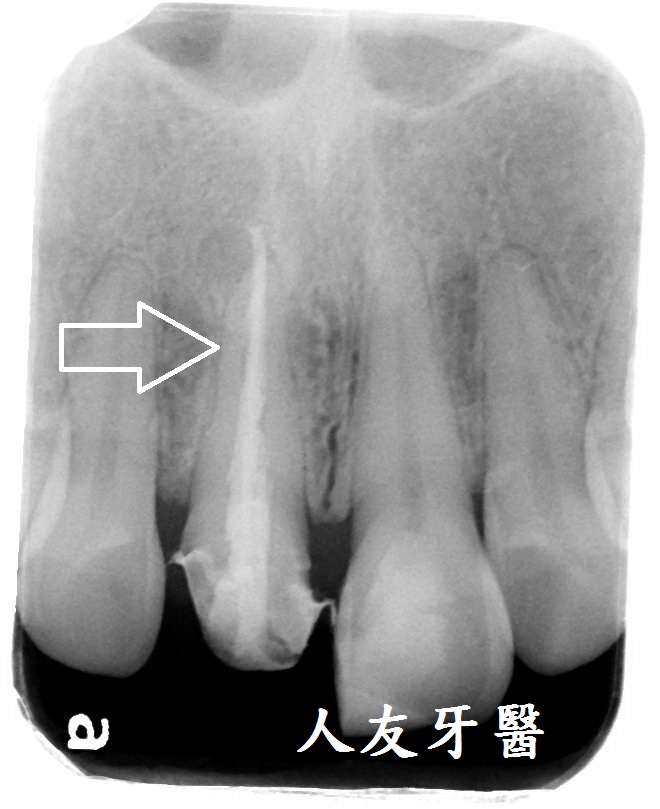

根尖病變一直長膿包還有救嗎?